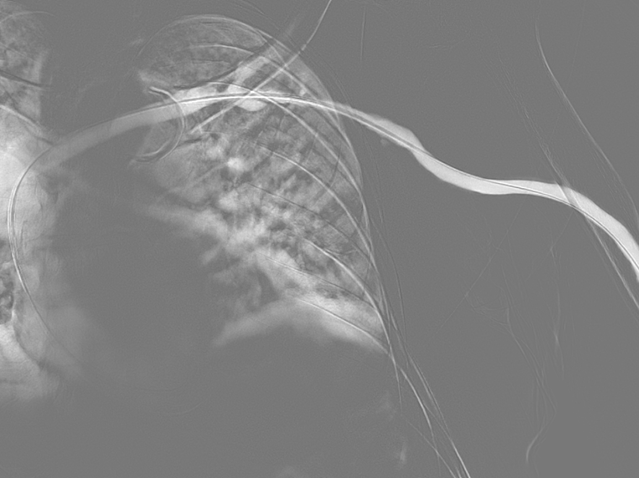

투석혈관 협착,

스텐트삽입술

시술 전

시술 후